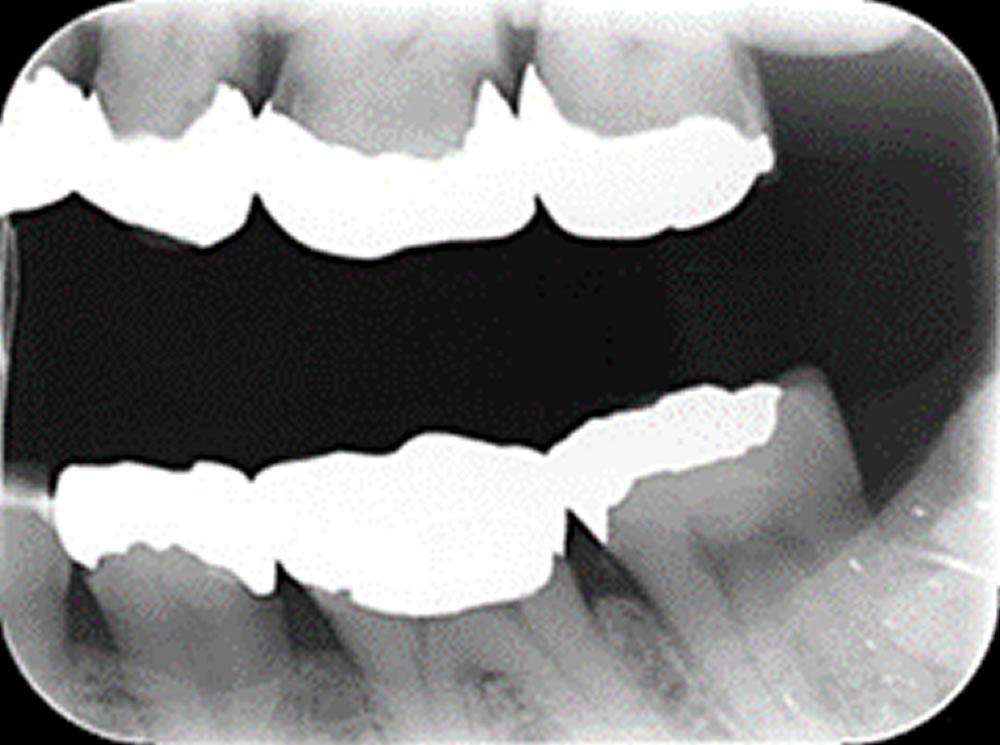

隙間のある銀歯をセラミッククラウンで治療した症例

隙間のある銀歯をセラミッククラウンで治療した症例 こちらの患者さまは、保険の金属の土台部分と歯質の間に隙間が認められたため、土台とかぶせ物の部分をはずして治療することになりました。 再発のリスクのことを考えたうえでセラミ […]